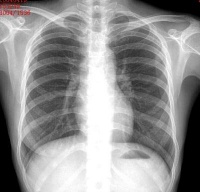

胸部正位平片